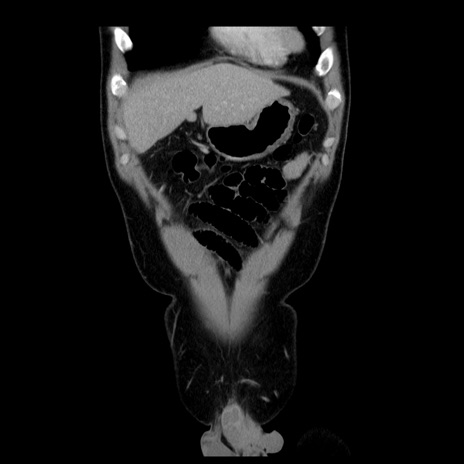

症例4(冠状断像)

【症例】30歳代男性

【主訴】腹痛、嘔吐

【現病歴】昨晩から突然の腹痛あり、その後嘔吐、軟便も出現。腹痛が改善しないため救急搬送となる。2日前にしめ鯖の食事歴あり。

【身体所見】意識清明、苦悶様、BP 135/90mmHg、BT 35.7℃、腹部:平坦、やや硬、心窩部〜臍部に自発痛、圧痛あり、筋性防御+、反跳痛-

【データ】WBC 8100、CRP 0.57